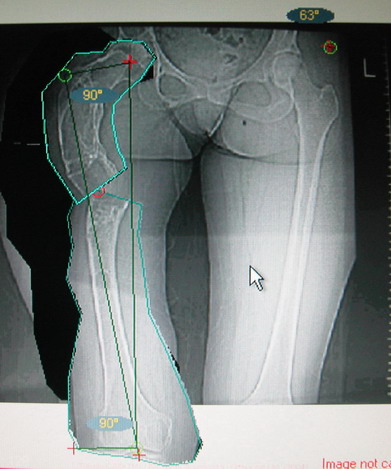

Поскольку в данном случае имеется дело с довольно большой деформацией с укорочением, одномоментная её устранение с внутренней фиксацией, чревато с одной стороны неправильной коррекцией, с другой, нейроваскулярными осложнениями.

Моё мнение, что двойная остеотомия бедра с аппаратом Илизарова + Гексаподный механизм, или Тэйлора, В данной ситуации является методом выбора. Я очень извеняюсь за качество прилагаемых снимков, в которых я постарался отразить разницу междe одной и двумя остеотомиями бедра.